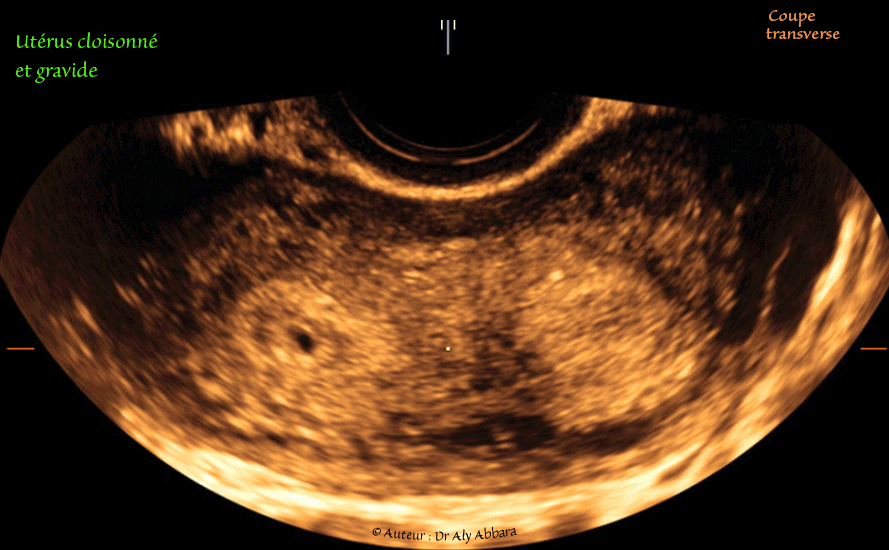

Utérus cloisonné partiellement et gravide (5 SA) :

• Images échographiques montrant, sur une coupe coronale (frontale) et transverse, un utérus malformé : cloisonné et gravide.

• Il s'agit d'une cloison épaisse, antéro-postérieure médiane divisant partiellement la cavité du corps utérin en deux compartiments, droit et gauche de tailles égales.

• Cette cloison musculaire est très large au niveau de sa base fundique (sur la coupe frontale), puis il se rétréci progressivement jusqu'à son extrémité distale qui atteint la zone de jonction du tiers moyen et inférieur de la cavité utérine, donc il s'agit d'une cloison partielle (U2a de la classification de ESHRE et ESGE - 2013).

• La surface extérieure du fond utérin est plate (sans l'indentation fundique extérieure ou sans sillon ou sans fissure ou sans scissure), ce qui permet de le différentier de l'utérus bicorne (ou utérus bicorporéal).

• On observe la présence d'un sac gestationnel débutant (5 SA) dans le compartiment droit de cet utérus.

• Dans les antécédents obstétricaux de cette patiente on note deux grossesses de déroulement normal et accouchements à terme.